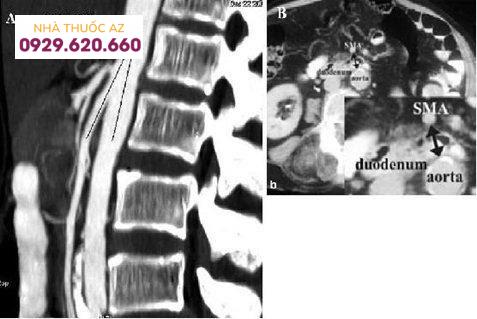

CT bụng và vùng chậu cho thấy: tá tràng bị chèn ép (mũi tên đen) giữa động mạch mạc treo tràng trên (mũi tên màu đỏ) và động mạch chủ bụng (mũi tên màu xanh).

Đo góc giữa ĐMTTT và ĐM chủ bụng. A, đo được 70. B, 320. Nguồn: Birsen Ünal et al. Superior mesenteric artery syndrome: CT and ultrasonography findings. Diagn Interv Radiol 2005; 11:91

Bệnh nhân nữ 7 tuổi, đau bụng trên, nôn dịch mật, ăn không ngon và sụt cân. Cân nặng 21kg, cao 1.23 m (cân nặng nhỏ hơn chiều cao). Không khai thác được bất cứ tiền căn về rối loạn tâm lý và quá trình tăng trưởng và phát triển. Nhập viện trong tình trạng lờ đờ, mất nước vừa, tim 100l/p, HA 116/63 mmHg, nhiệt độ 370. Khám lâm sàng bình thường. Hình A, tái tạo Sagittal đo góc hẹp 14 độ. Hình B, đo khoảng cách hẹp 11 mm. Siêu âm: góc ĐMTTT và ĐM chủ bụng = 10 độ